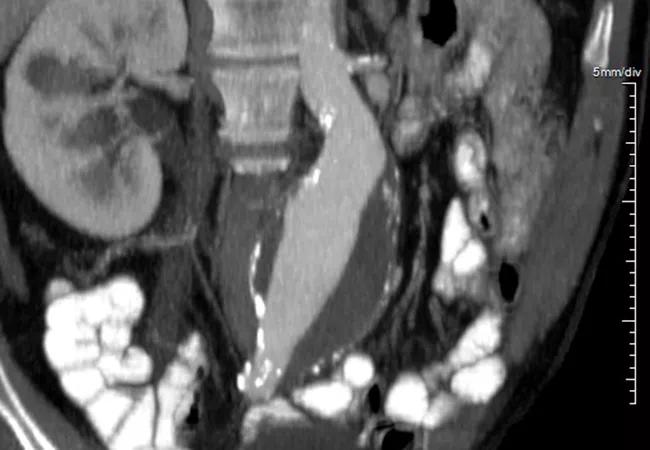

imaging scan of abdominal organs

Both transperitoneal (TP) and retroperitoneal (RP) approaches to abdominal aortic aneurysm (AAA) repair are safe in women, so patient anatomy and surgeon preference should drive decision-making about choice of technique in female patients. So concludes a retrospective midterm outcomes study by Cleveland Clinic researchers published in Vascular (2025;33[3]:511-519).